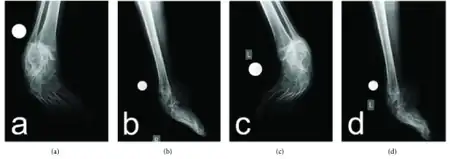

| Onion bulb formations in a nerve biopsy in a case of HMSN type I | |